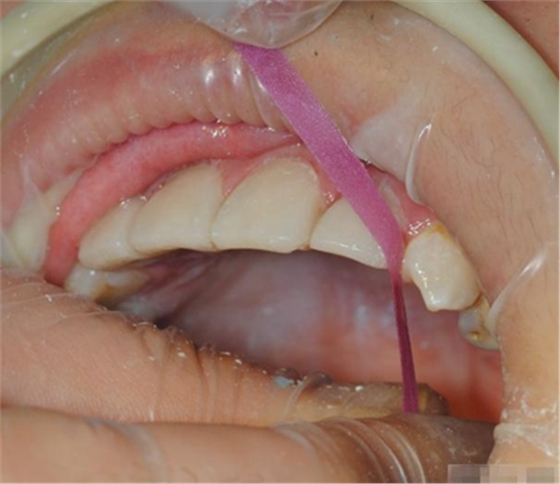

鄰接面可以使用拋光條和不同粒度的拋光膏

拋光條

使得鄰接面的拋光更容易進(jìn)行

中間一段沒(méi)有涂砂是光的,用于進(jìn)入鄰接面.

每一根拋光條都有兩個(gè)粒度的表面:粗/中,細(xì)/超細(xì).

顏色標(biāo)識(shí): 由深(粗)到淺(超細(xì)).

聚酯背襯非常有韌性,經(jīng)得起牽拉,比起金屬拋光條對(duì)牙齦更溫和